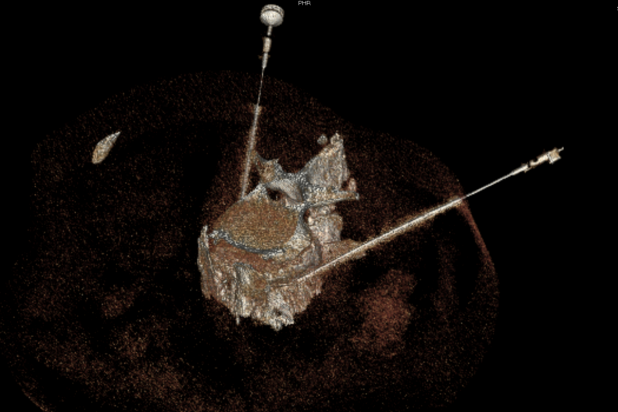

疼痛科团队术前认真讨论,并跟家属充分沟通手术风险,最后确定手术方案。在CT影像的帮助下,疼痛科医师们顺利为患者实施CT引导下腰交感神经射频消融+无水乙醇毁损术。手术后患者便感觉双下肢疼痛和麻木症状减轻,体温监测示其双侧足背皮温升高1.5℃-2.0℃。次日上午患者感觉双下肢疼痛和麻木症状显著减轻,夜间睡眠质量大幅改善,对治疗效果感到满意。

目前,疼痛科开展有两种微创介入手术方法治疗干预糖尿病性周围神经痛。一种方法是腰交感神经节射频消融+无水乙醇毁损术,通过CT影像精准定位L2椎体下缘、L2-3椎间盘和L3椎体上缘,对腰交感神经节实施热凝和化学双重毁损,阻断交感神经对下肢血管收缩异常指令,从而扩张血管以改善组织血供,以缓解疼痛和麻木症状。另一种方法是脊髓电刺激器植入术(SCS),通过植入式电极向脊髓特定节段输送低强度电脉冲,从而阻断或调制疼痛信号传导,有效缓解疼痛。